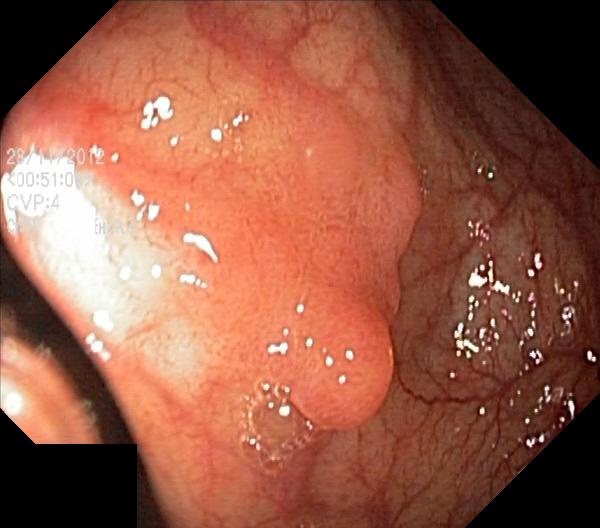

The Kvaris-SEG (Jha et al., 2020c) training dataset can be downloaded from https://datasets.simula.no/kvasir-seg/. It contains 1,000 polyp images and their corresponding ground truth mask as shown in Figure 1. The dataset was collected from real routine clinical examinations at Bærum Hospital in Norway by expert gastroenterologists. The resolution of images varies from to pixels. Some of the images contain a green thumbnail in the lower-left corner of the images showing the scope position marking from the ScopeGuide (Olympus) (see Figure 2). We annotate another separate dataset consisting of 160 new polyp images and use the resulting dataset as the test set to benchmark the participants’ approaches. Figure 2 shows some examples of test images used in the challenge.